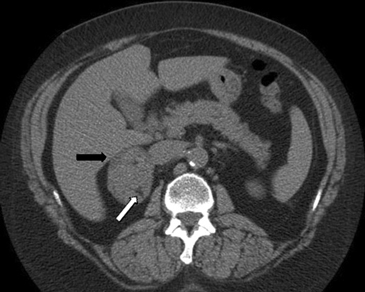

e) Biopsia percutánea guiada por TAC

En la actualidad su uso es excepcional y su indicación esta reservada para casos en que las técnicas no invasivas no son diagnosticas y en casos en que se sospecha un linfoma y es necesario tipificarlo. En el lado derecho si la masa es pequeña se prefiere el abordaje transhepático (Figura 16 a) y en el lado izquierdo la vía dorsal posterior (Figura 16 b).

La vía transhepática sólo se realiza con aguja fina, de manera que si en el lado derecho es necesario obtener mayor cantidad de tejido, la biopsia se realiza con una aguja de tipo trucut pero el acceso tiene que ser por vía dorsal posterior.